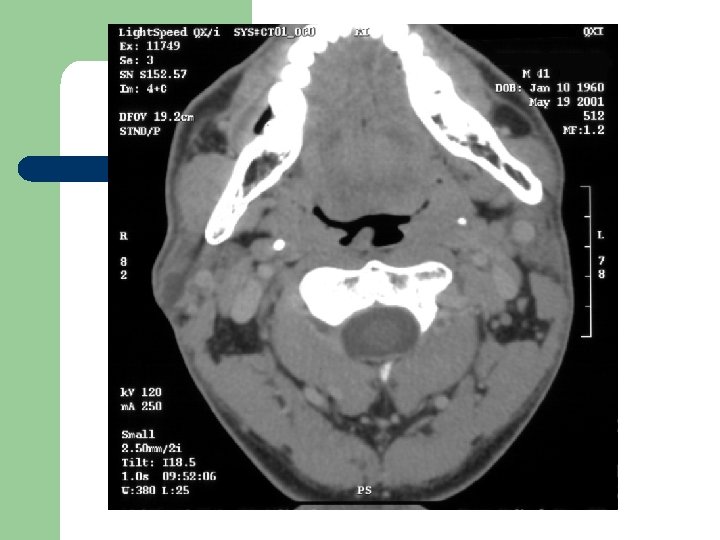

Radiological Evaluation l CT Scan and MRI: To determine the extension of the disease.